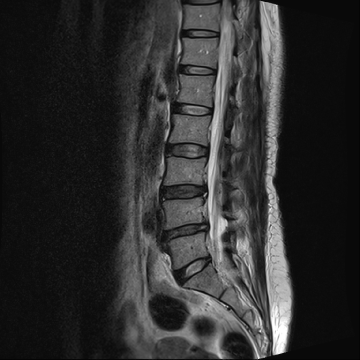

허리 디스크 수술 전·후

2021.10.19

2023.01.09